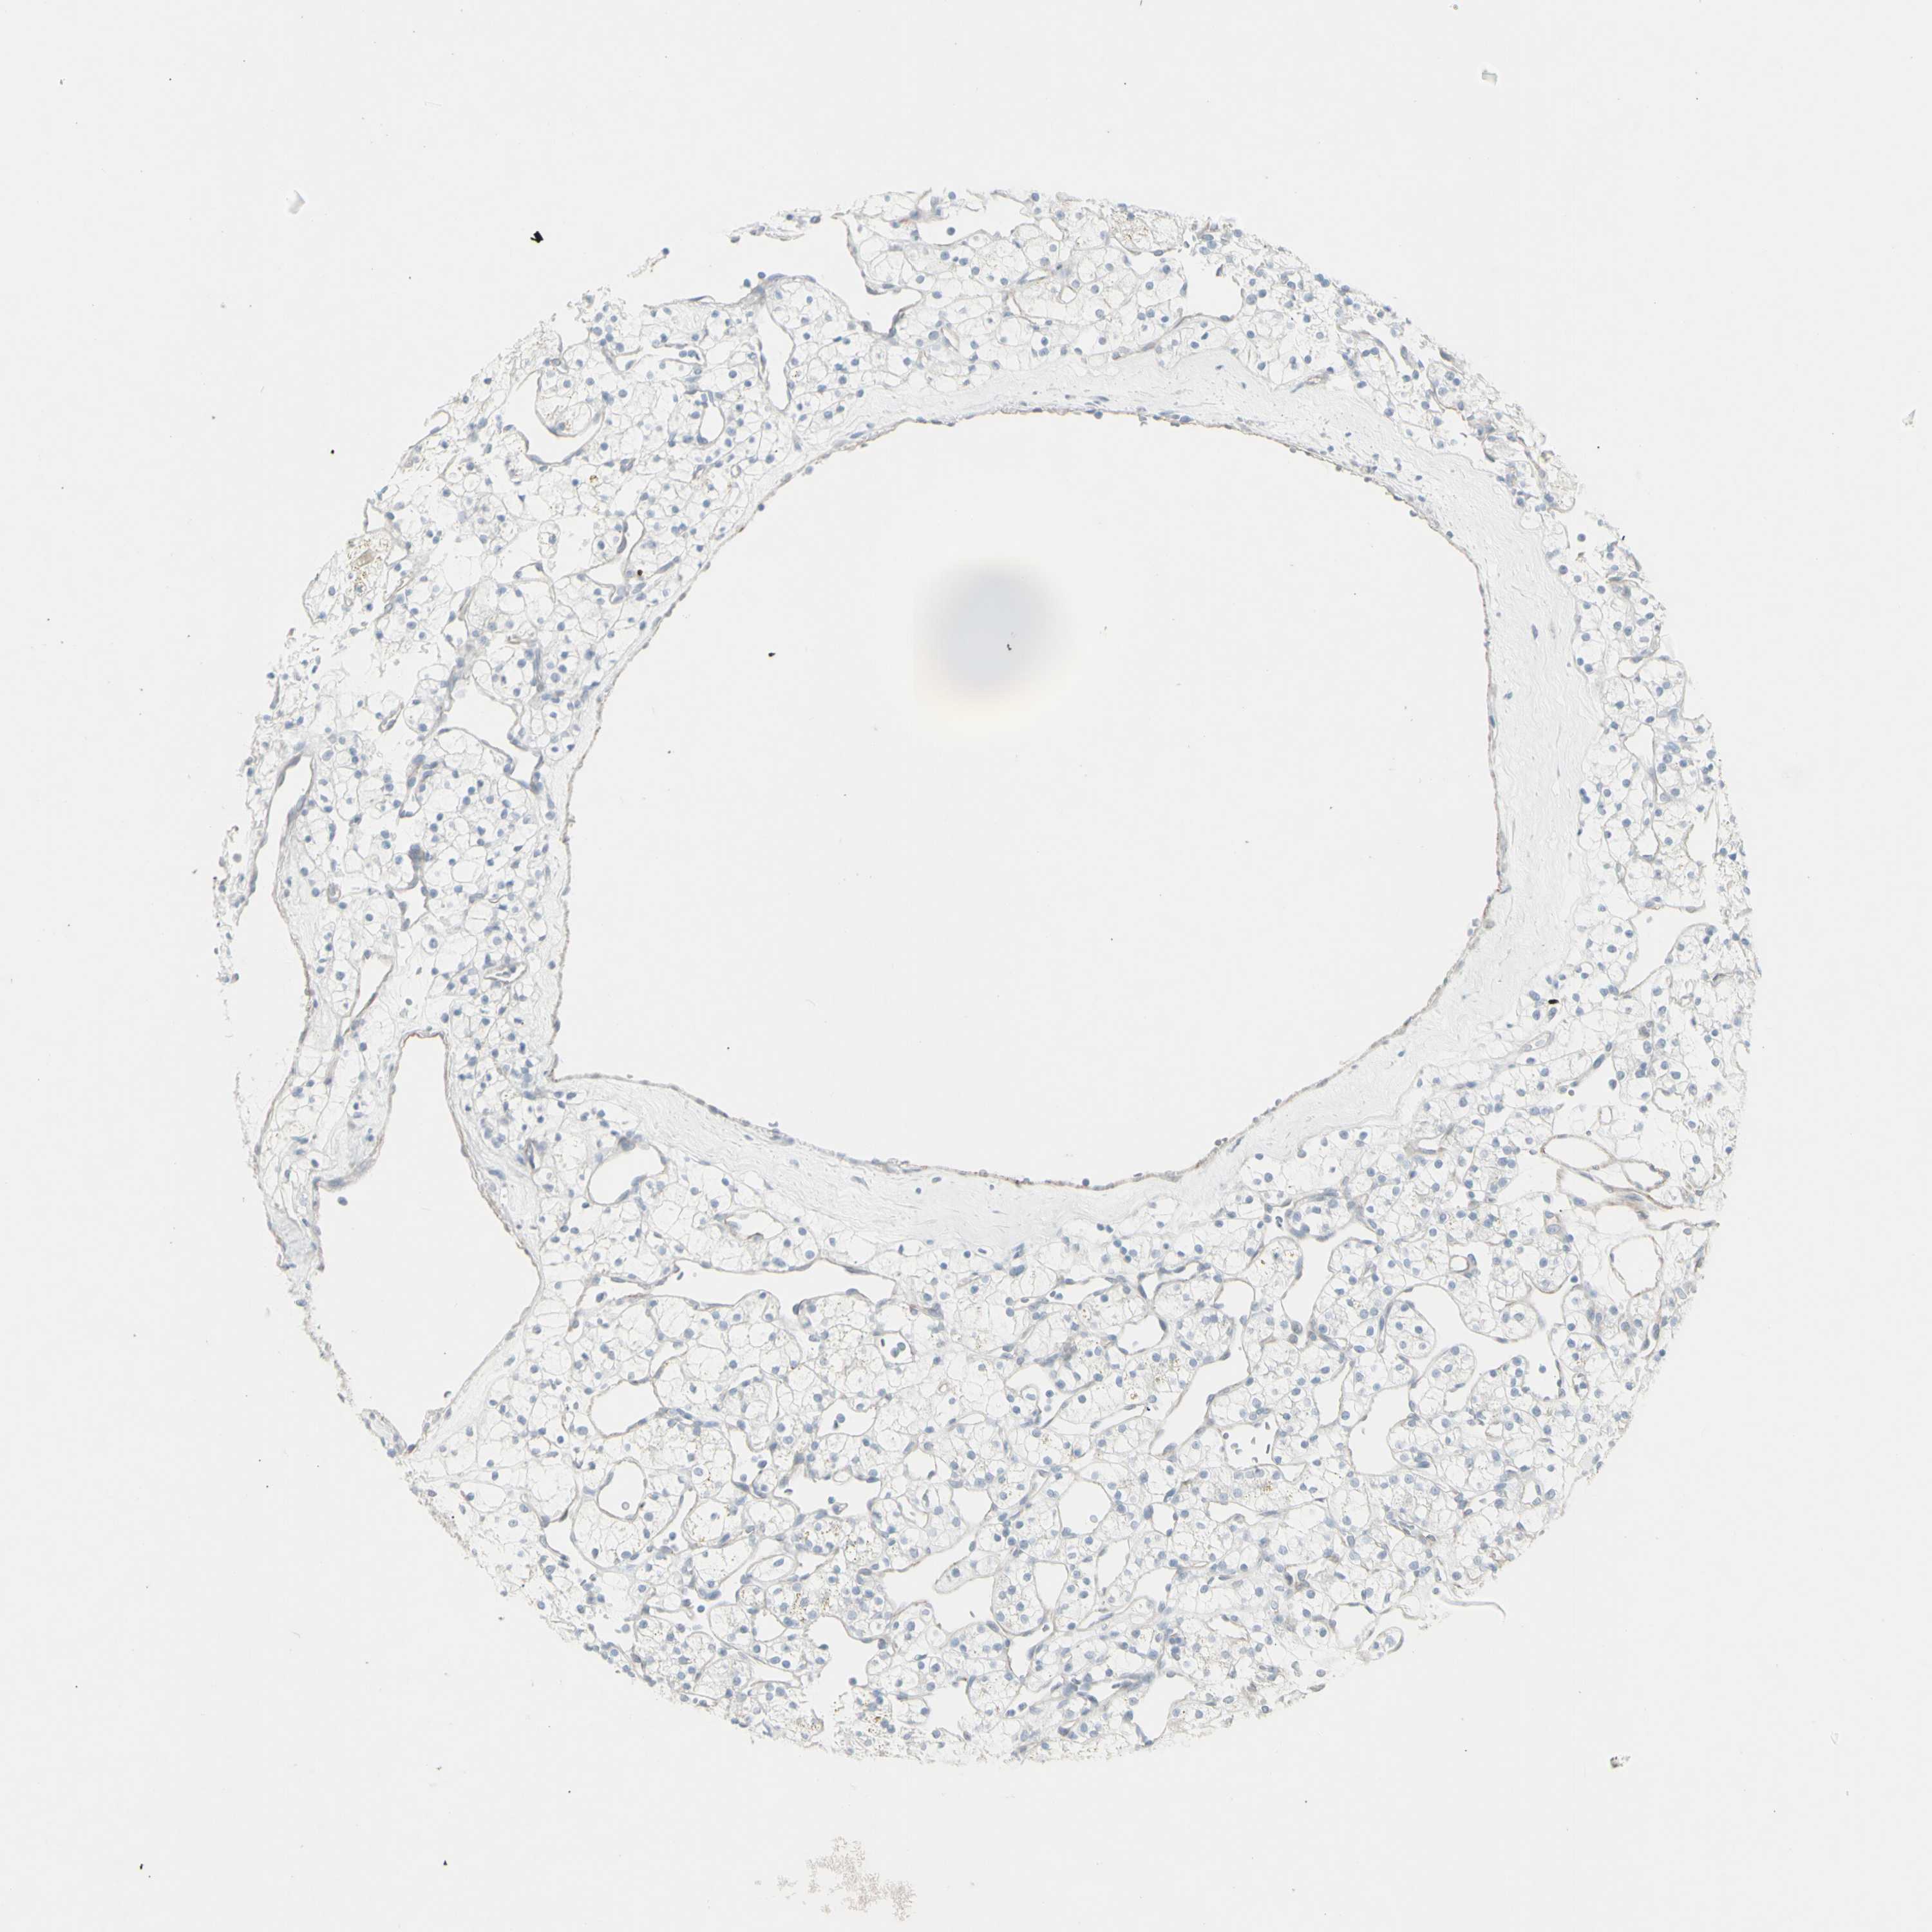

KIDNEY RENAL CLEAR CELL CARCINOMA (VALIDATION) - Interactive survival scatter ploti

The Survival Scatter plot shows the clinical status (i.e. dead or alive) for all individuals in the patient cohort, based on the same data that underlies the corresponding Kaplan-Meier plots. Patients that are alive at last time for follow-up are shown in blue and patients who have died during the study are shown in red.

The x-axis shows the expression levels (FPKM) of the investigated gene in the tumor tissue at the time of diagnosis. The y-axis shows the follow-up time after diagnosis (years). Both axes are complimented with kernel density curves demonstrating the data density over the axes. The top density plot shows the expression levels (FPKM) distribution among dead (red) and alive patients (blue). The right density plot shows the data density of the survived years of dead patients with high and low expression levels respectively, stratified using the cutoff indicated by the vertical dashed line through the Survival Scatter plot. This cutoff is automatically defined based on the FPKM cutoff that minimizes the p-score. The cutoff can be changed by dragging the vertical line or by entering a cutoff value in the square labeled "Current cut-off".

Under the Survival Scatter plot the p-score landscape (black curve; left axis) is shown together with dead median separation (red curve; right axis). Dead median separation is the difference in median mRNA expression between patients who have died with high and low expression, respectively. It is calculated as follows: median FPKM expression of dead patients with high expression - median FPKM expression of dead patients with low expression. This is intended to aid the user in visually exploring custom cutoffs and the associated p-scores and dead median separation.

Individual patient data is displayed and can be filtered by clicking on one or more of the category buttons on the top of the page. Categories describing expression level and patient information include: high, low, alive, dead, female, male and tumor stages. The scale of the x-axis can be toggled between linear and log-scale by clicking on the "x log" button. Mouse-over function shows TCGA ID, patient information and mRNA expression (FPKM) for each patient.

& Survival analysisi

Kaplan-Meier plots summarize results from analysis of correlation between mRNA expression level and patient survival. Patients were divided based on level of expression into one of the two groups "low" (under cut off) or "high" (over cut off). X-axis shows time for survival (years) and y-axis shows the probability of survival, where 1.0 corresponds to 100 percent.

YBX2 is not prognostic in Kidney Renal Clear Cell Carcinoma (validation)

TCGA RNA samplesi

RNA-seq data is reported as average FPKM (number Fragments Per Kilobase of exon per Million reads), generated by the The Cancer Genome Atlas (TCGA) .

Normal distribution across the dataset is visualized with box plots, shown as median and 25th and 75th percentiles. Points are displayed as outliers if they are above or below 1.5 times the interquartile range. FPKM values of the individual samples are presented next to the box plot.

Average pTPM 0.5

Number of samples 100